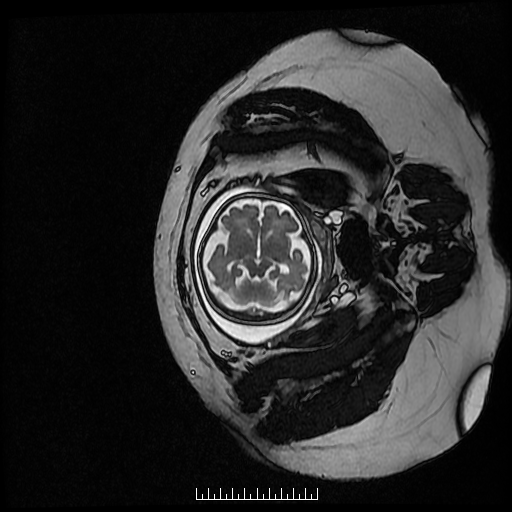

1.胎儿MRI扫描:胎儿成像的首选检查手段为超声,其操作简单,无创,快速,实时,价格低廉,特别适合大范围人群筛查,但也有不足之处,如超声难以穿越胎儿颅骨,视野偏小,对母体肥胖,有子宫肌瘤,羊水过少,多胎等情况时,对胎儿显示效果欠佳。磁共振则不受到这些因素影响,对羊水过少,双胎,及孕晚期胎头入盆或胎儿颅骨骨化,胎儿磁共振可以起到明显的补充作用。